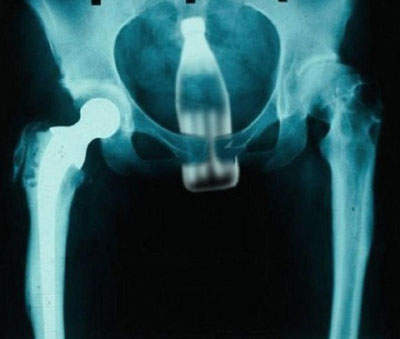

凌凌漆的P.S:不過眾多異物插入照還是不及這種給我的震撼~如下圖!

(如果這還是個男的更屌)